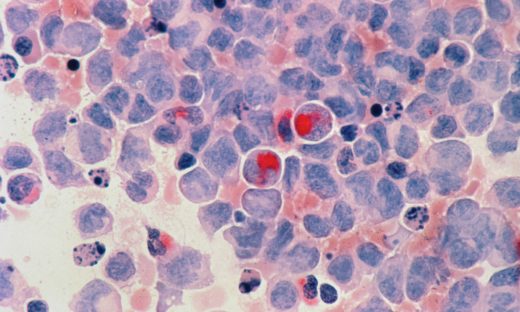

さらに、2010年の細胞レベルの研究¹²では、アセトアミノフェンがラットの脳細胞に「アポトーシス(細胞が自分から死ぬ現象)」を起こすことが明らかになりました。そして2022年の研究¹³では、脳の細胞同士のつながり(神経突起)や細胞の骨組み(細胞骨格)に異常が出ることが分かりました。